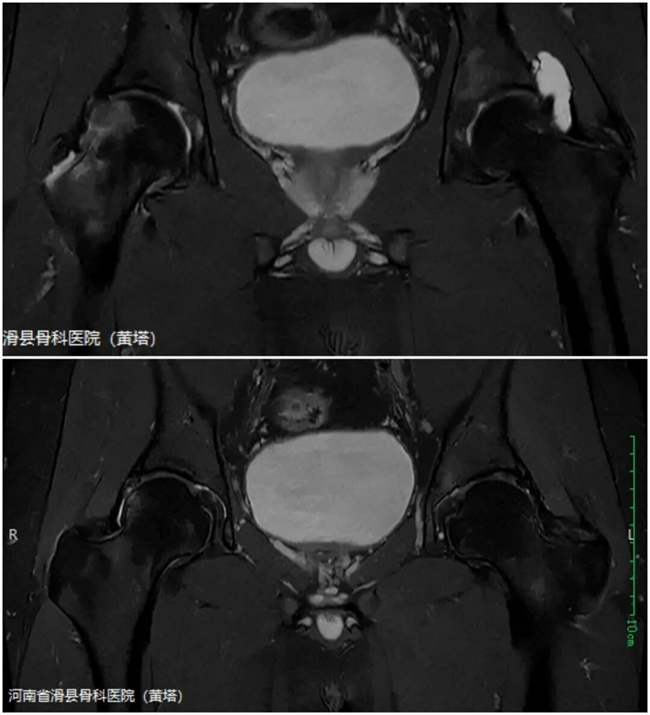

一、患者黄某某,男,27岁,患者右髋疼痛2月余,右侧髋关节前侧压疼明显,活动受限。为求进一步治疗,来到我院请专家会诊,通过各位专家会诊查体、查看影像资料并细致认真的分析后,诊断:右髋关节撞击综合征,意见:建议保守。